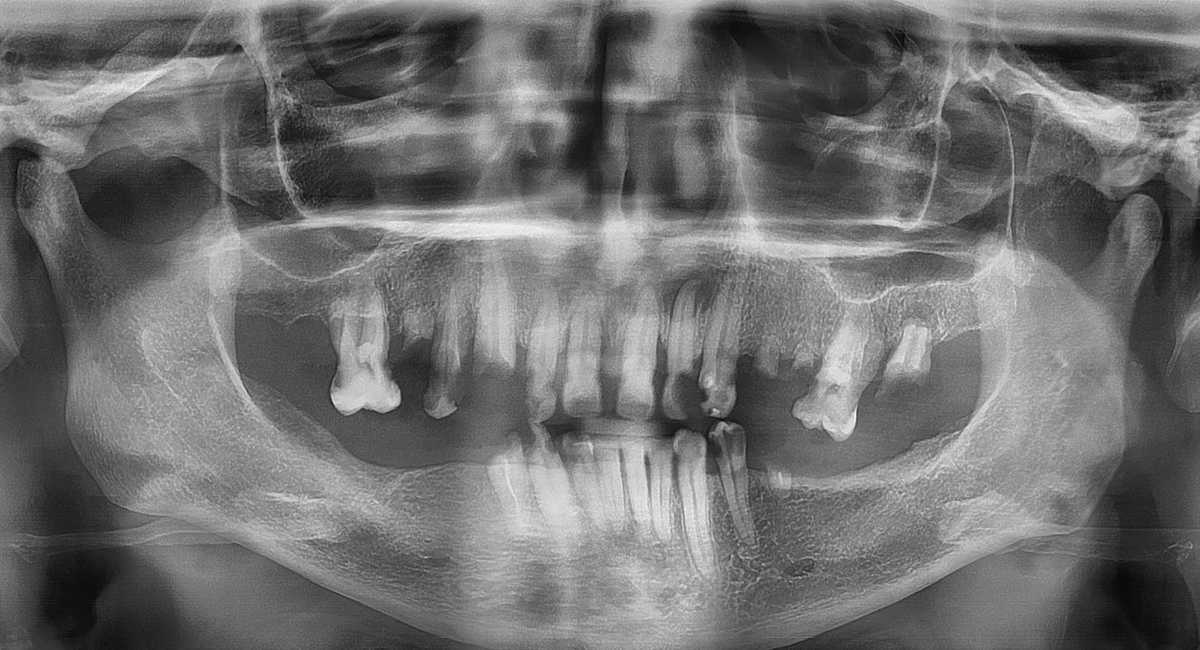

Елена Вячеславовна обратилась в клинику Estetus после отказа в проведении аналогичной процедуры в другой клинике. Ее собственные зубы практически отсутствовали, оставшиеся единицы были сильно разрушены и подвижны, нарушая прикус и создавая серьезные эстетические проблемы. Пациенту хотелось лишь одного — снова нормально питаться простой пищей и свободно общаться, не испытывая дискомфорта.

Бобоев Назар Суванкулович, врач клиники Estetus, внимательно изучив состояние полости рта пациента, разработал детальный план лечения. Было принято решение провести полное восстановление зубного ряда методом All-on-6, позволяющим восстановить функциональность зубов всего за 3 дня.

Методика V-II-V была применена для верхней челюсти ввиду недостатка костной ткани, благодаря чему импланты установлены под особым углом, обеспечивающим надежную фиксацию без дополнительной остеопластики.

При восстановлении верхних зубов используется уникальная методика V-II-V, предполагающая установку двух центральных имплантов вертикально («II») и четырёх угловых, расположенных под наклоном («V»), формирующих своеобразную конструкцию типа «Ви-ту-Ви». Такой подход оптимален при недостатке кости и обеспечивает надежную основу для фиксации конструкции.